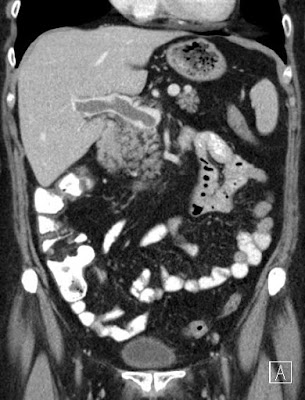

Szerző: admin | okt 25, 2011 | Mesenteric ischemia, Thrombosis, Vascular

circumferential enhancement in the mesenteric vein850092011.1021